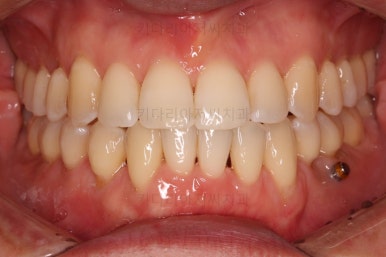

부산비수술교정 키다리아저씨치과에서 시행한 이번 치료의 결과입니다.

옆모습이 주걱턱 느낌이 많이 없어졌고 볼록하던 아랫입술도 뒤로 들어갔어요. 앞니가 거꾸로 물리지 않게 되어 웃거나 말하는 모습도 자연스러워졌어요.

아랫니 갯수가 모자라고 중앙이 맞지 않았고 짝이 안맞는 상황이었으나 비교적 잘 마무리를 했어요.

거꾸로 물리는 상황이 개선되었기 때문에 앞니나 어금니의 교합은 이전과 비교할 수 없을만큼 좋아졌지요.

전후 모습을 비교해 보겠습니다.

왼쪽이 치료 전, 오른쪽이 치료 후 모습입니다.